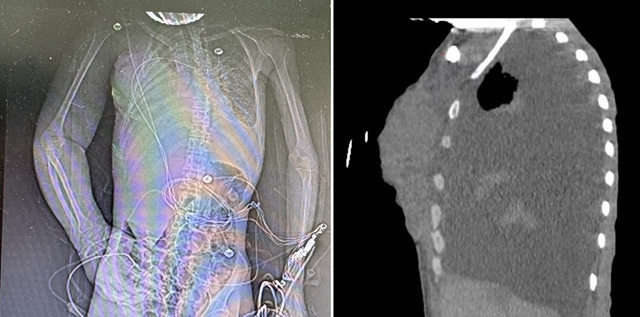

入院时影像检查

刘女士入院时呼吸急促、极度虚弱,轻微活动即可导致血氧饱和度急速下降,只能完成床旁检查。床旁彩超提示双侧大量胸腔积液,右侧液层深12cm,左侧10cm,双肺受压明显,呼吸衰竭。万霞医师立即为其行双侧胸腔穿刺置管引流,并予呼吸机支持,呼吸症状暂时得到缓解。检验结果显示:恶病质、重度贫血、呼吸衰竭、酸中毒、肝功能损害,肿瘤标志物显著升高。